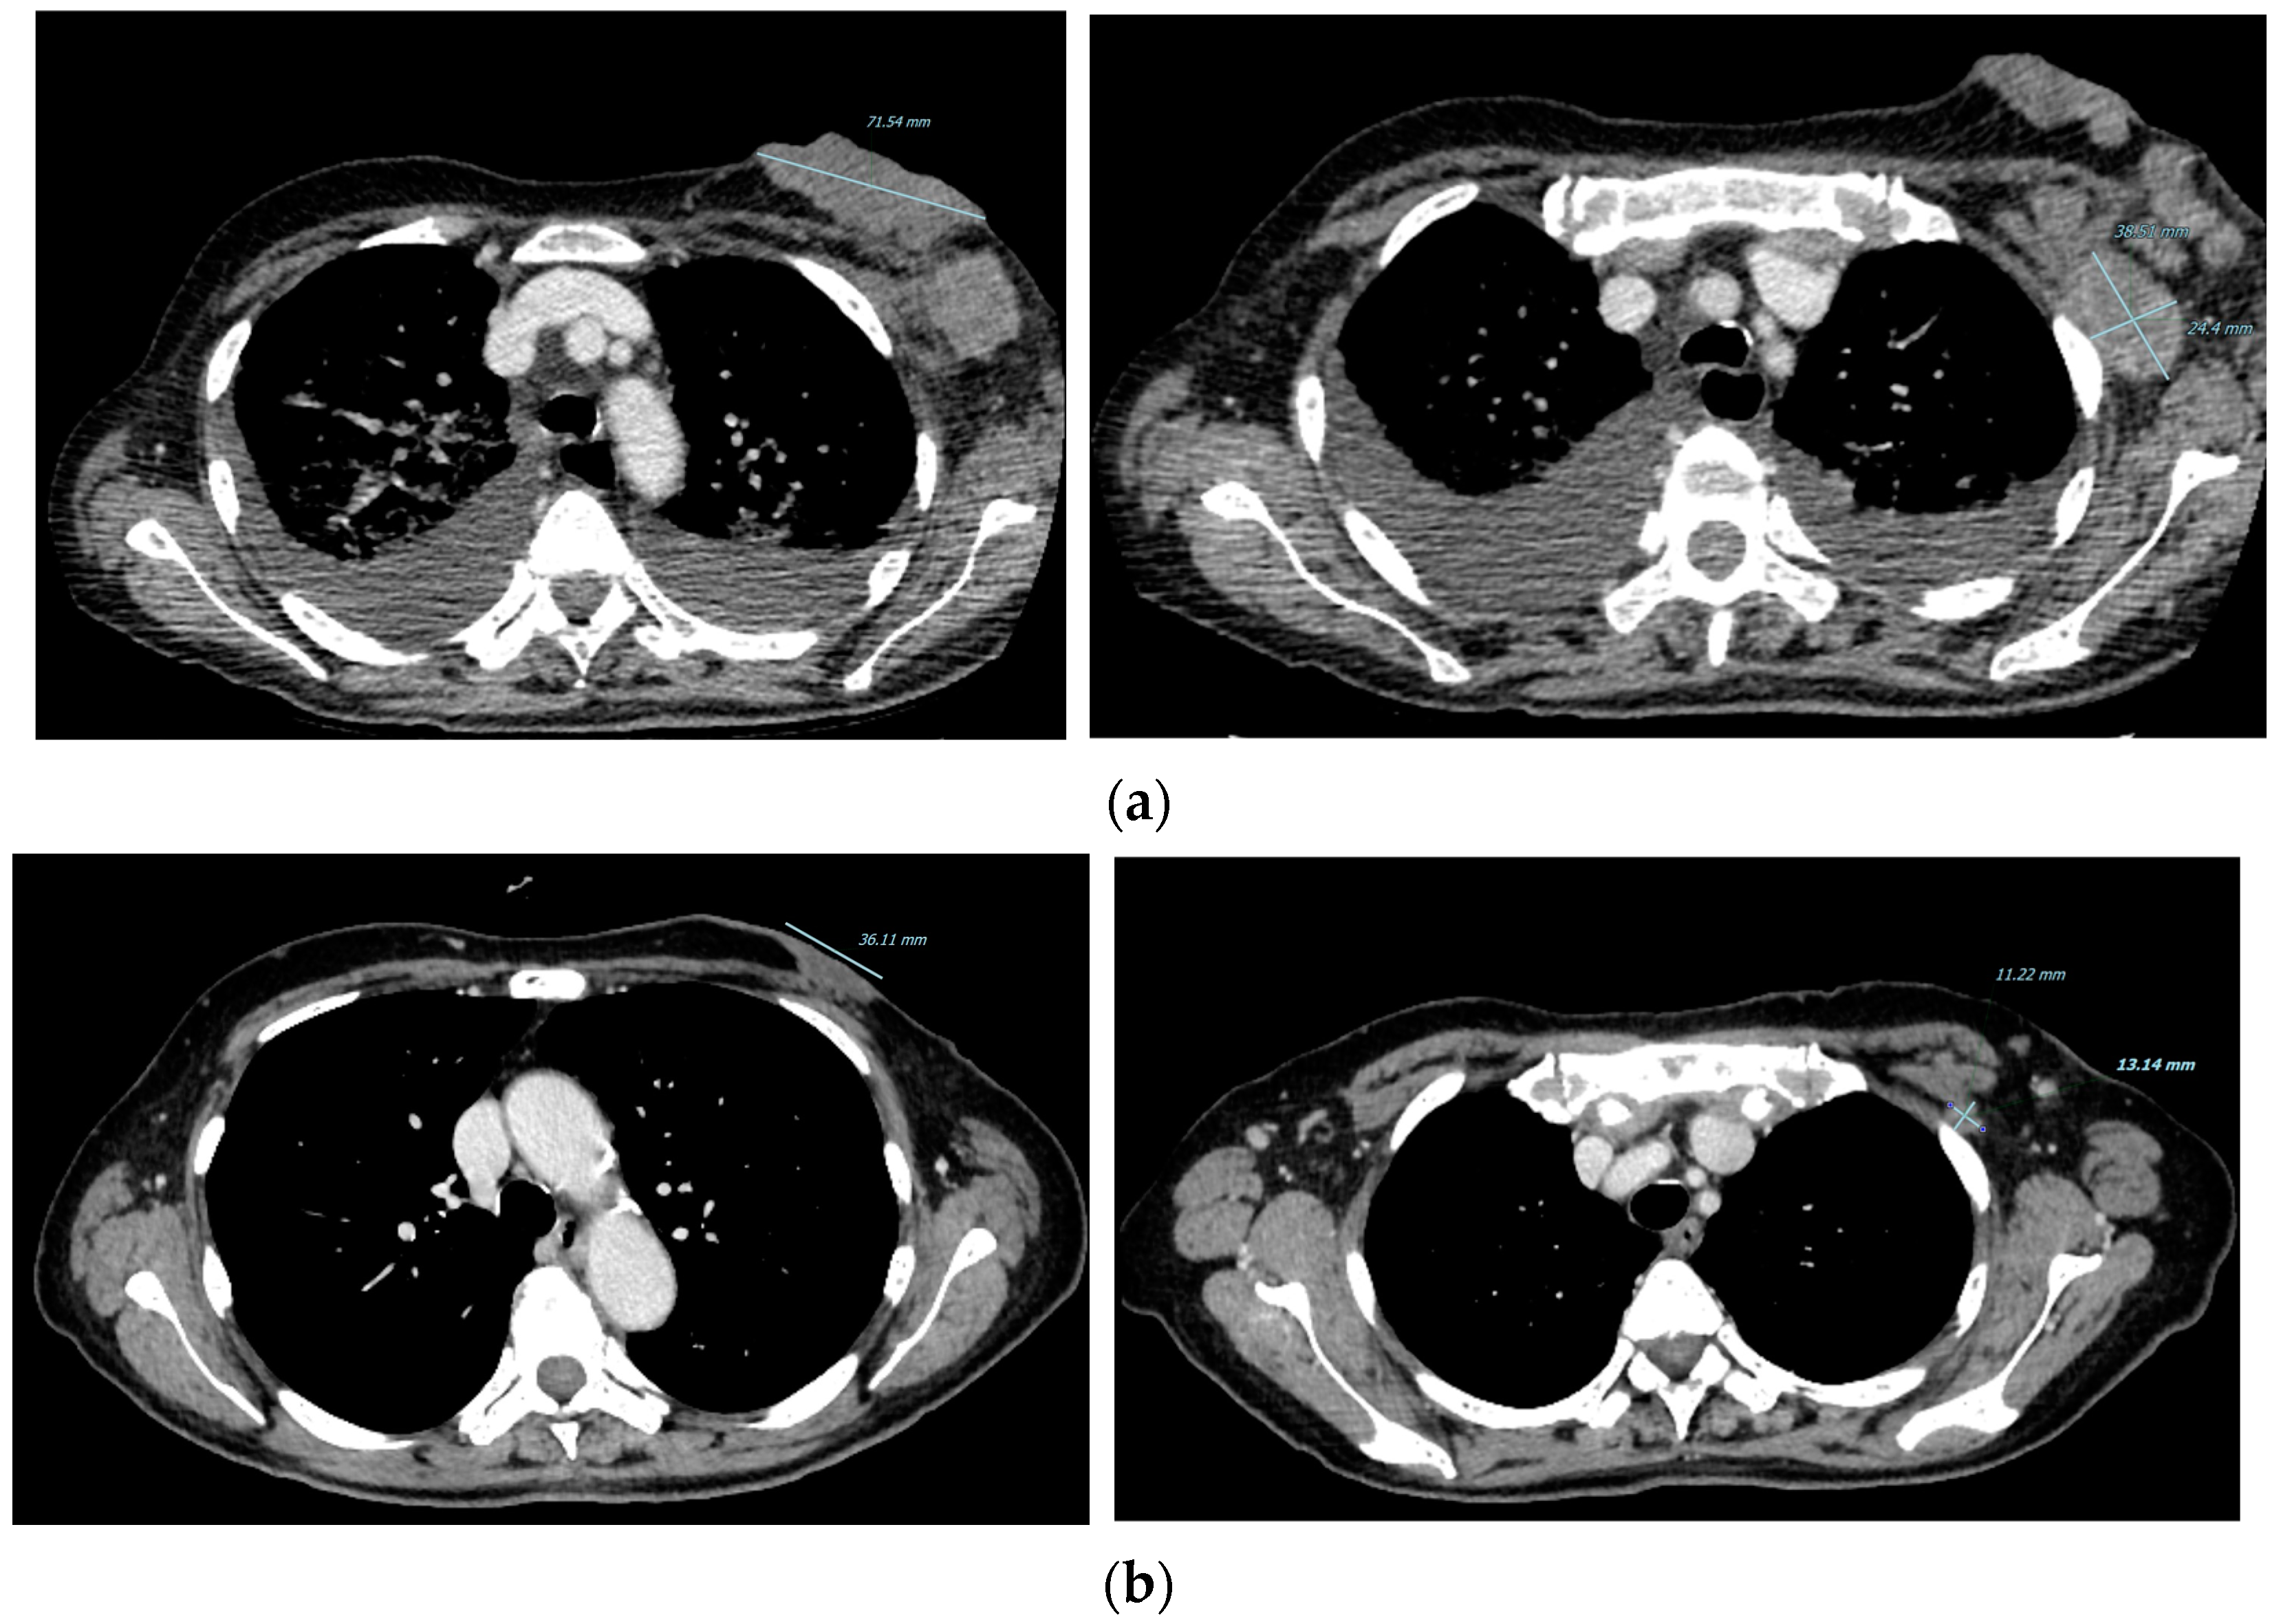

2. Case Presentation